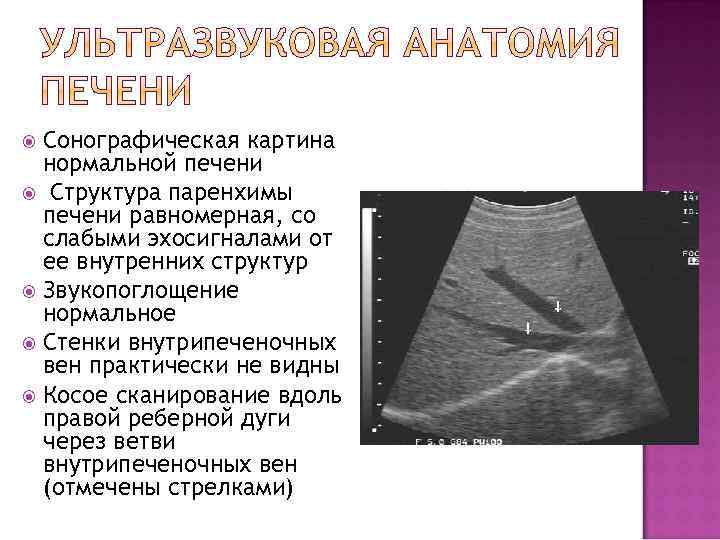

Сонографическая картина нормальной печени Структура паренхимы печени равномерная, со слабыми эхосигналами от ее внутренних структур Звукопоглощение нормальное Стенки внутрипеченочных вен практически не видны Косое сканирование вдоль правой реберной дуги через ветви внутрипеченочных вен (отмечены стрелками)